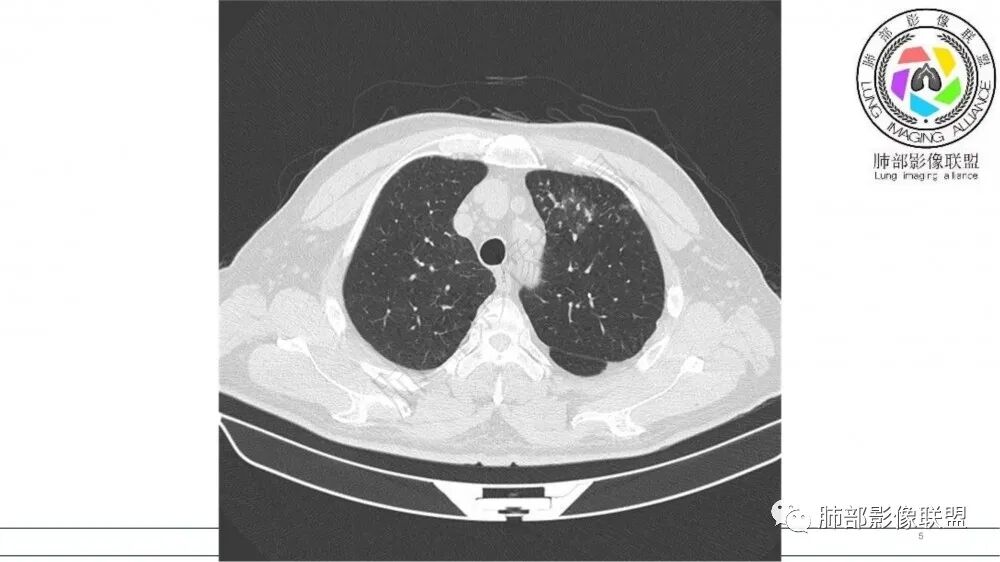

猜个鳞,沿支气管塑型生长,周围小花小草,肺门及纵隔淋巴结增大,吸烟老年男。鉴别TB

左肺上叶前段支气管内铸形生长软组织影,增强后均匀强化,远侧见斑片状磨玻璃影。考虑恶性病变,粘表?粘液腺?

考虑恶性占位,沿支气管塑型生长,增强未见明显强化,首先考虑鳞癌,鉴别APBA及结核,感觉不像,最后挂上小细胞肺癌。

病灶有强化,粘液栓不考虑。沿着支气管生长,远端小花小草,恶性首先考虑。鉴别结核

老年男性,左肺上叶前段支气管内铸形阴影,增强后病灶不均匀强化,内部有坏死?远端可见斑片状阴影(阻塞性肺炎)。考虑恶性病变,老年人,鳞?类癌?粘表不能排除。

左肺上叶前段支气管杵状指样扩张,内见实性组织阻塞性,并强化明显,边缘饱满,周边多发小斑点影,小花小草征,老年男性,长期吸烟史,方向恶性,首选支气管内浸润鳞Ca可能性大。

男,70岁,吸烟史,咳嗽,胸闷憋气一个月,左肺上叶不规则形软组织密度影,病灶沿支气管走形,周围见粟粒及棉絮样稍高密度影,增强扫描病灶内见少许坏死,考虑鳞癌可能,鉴别结核。

支气管壁病变

左肺上叶前段支气管管壁增厚,腔内软组织填充,有强化,远段阻塞性肺炎,考虑恶性

老年男性,肺气肿,吸烟史,左肺上支气管腔内铸型高密度影,呈指套状,远端多发树芽,增强不均匀强化,考虑鳞癌,鉴别小细胞癌

男性,吸烟,肿块沿左肺上叶支气管内生长,增强后病灶不均匀强化,考虑小细胞肺癌

70岁男,吸烟史,左肺上叶不规则肿块,轻度强化,前段支气管增厚,周围可见阻塞性小花小草,考虑鳞癌

老年男性,吸烟史,左肺上叶沿支气管塑型生长软组织肿块,轻度强化,周围小花小草,肺门及纵隔淋巴结增大,倾向恶性病变,鳞癌?粘表?

老年男性,吸烟史,左肺上叶支气管铸形,轻度强化,周围可见阻塞性小花小草,考虑鳞癌

B3指套征,常规不是鳞癌就是ABPA,有强化丶血管造影征,倾向于鳞癌

老年男性,左侧支气管腔塑形生长肿块,边缘可见多发小结节,增强后不均匀轻度强化,考虑恶性,鳞癌可能大,鉴别结核

老年男性,吸烟史,左肺上叶支气管塑形生长肿块,整体边缘较圆钝,不均匀强化,血管走形,形态较纤细,病灶远端可见花草样改变,恶性,先考虑小细胞癌鉴别鳞癌

老年男性,吸烟史,左肺上叶支气管铸形,变窄,轻度强化,周围阻塞性炎症,左肺门肿大淋巴结,考虑恶性,小细胞鉴别鳞癌

小花小草,支气管阻塞,考虑鳞癌,鉴别腺癌,结核,及淋巴瘤

老年吸烟男,左肺上叶支气管堵塞,远端小花小草,纵隔未见肿大淋巴结,考虑鳞癌,建议进一步支气管镜检查

左肺上叶支气管铸形生长,远端阻塞性炎症,增强后病灶有强化,坏死区明显。考虑中央型肺癌,鳞癌?小细胞癌?

左肺上叶尖后段支气管近端截断,远端见高密度铸型,远侧见阻塞性改变,老年男性,吸烟史,考虑恶性,鳞癌。ABPA代排

老年男性,吸烟史,左肺上叶不规则肿块,支气管铸型生长,增强轻度强化,周围可见阻塞性小花小草,考虑鳞癌

老年男性,长期吸烟史。左上肺前段沿支气管走形的指套样病变,增强可见病灶强化(排除结核、ABPA(也无气喘症状)),远端多发点状高密度影。考虑恶性肿瘤,鳞癌可能性大。

老年男性,左肺上叶支气管内铸形影,远端阻塞炎症,小花小草,轻度强化,考虑恶性病变,鳞?小?粘表不能排除。

老年男性,吸烟史,左肺上叶沿支气管生长指样影,边缘膨隆,轻度强化,周围斑点影,考虑恶性,鳞癌?

指套征明确吧

有强化吧,淋巴结大

恶性

指套征,扩张支气管内软组织强化,远侧肺野阻塞性炎,纵隔、左肺门肿大淋巴结;老年男性,吸烟,考虑鳞癌,鉴别小

小花小草,铸型粘液拴,左上叶支气管壁增厚,腔内可见软组织结节,粘液无强化,伴随血管粗细不均,老年,吸烟,定性恶性,磷癌

老年男性,术前检查肺气肿背景,左肺上叶结节,沿支气管蠕虫样生长,左肺门及纵隔淋巴结肿大,增强扫描不均匀强化,血管包绕,结合吸烟史,考虑小细胞肺癌。

老年吸烟男性,尖前段支气管内塑形生长,增粗蠕虫样,没有肺不张(排除鳞癌?),远端少许阻塞肺炎,增强低强化,锁定小

老年男性,吸烟,指套征,蠕虫征,阻塞性炎症不严重。可见血管穿行,密度均匀,轻度强化,首先考虑小细胞肺癌。鉴别鳞

2021年8月6日晨读病例结果:小细胞肺癌

指套征:是影像征象,胸部平片表现为手指状密度增高影,以肺门为中心呈放射状分布,CT显示扩张支气管内低密度黏液栓形成或实性病变,呈管状、树枝状或卵圆形密度增高影;支气管扩张伴近端梗阻时,扩张支气管内部黏液分泌物不能排出而形成。可以伴随远端空气潴留征、阻塞性炎症。